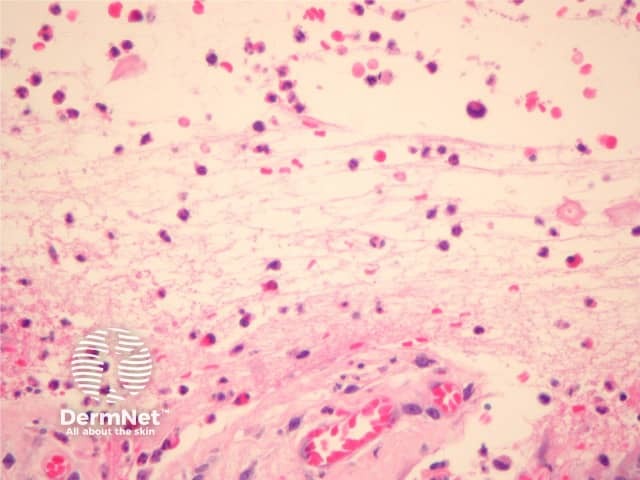

Established blister: The blister is subepidermal and contains fibrin and large numbers of inflammatory cells including eosinophils (figures 2, 3). The eosinophils may be very dense in areas and form small abscesses in the superficial dermis.

Figure 3